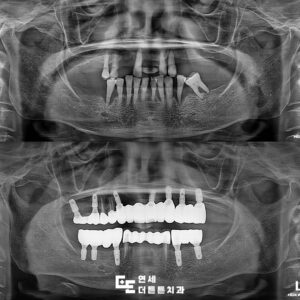

환자분은 70대 여성분으로

기존에 사용하던 임시 틀니의 불편함으로

최종 틀니 제작을 위해 내원해 주셨는데요.

1년 전, 내원 당시 본원에서 다수의 치아를

발치하고 위쪽 임시 틀니를 제작하셨습니다.

진단 결과, 현재는 위, 아래

완전 무치악 상태였으며

다양한 치료 방법에 대해

충분한 설명을 드렸으나

환자분의 사정에 의해 위, 아래

완전 틀니를 진행하기로 하였습니다.

평소 사용 중이시던 임시 틀니인데요.